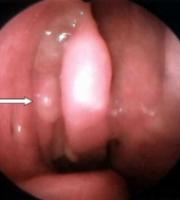

Polip jest to rozrost błony śluzowej nosa, o podłożu zapalno - alergicznym. Jest on chorobowo powiększona formą migdałka gardłowego. Migdałek gardłowy umiejscowiony jest w górnej części gardła, u samego dołu podstawy czaszki, dokładnie w punkcie, gdzie jama nosowa przechodzi w gardło. Jest zbudowany z krtani limfatycznej, a jego zadaniem jest - podobnie zresztą jak w przypadku migdałków podniebnych - ochrona przed zakażeniami. Z rozmaitych przyczyn może dojść do przerostu migdałów gardłowych i powstawania tzw. polipów. Powiększenie się migdałków powoduje stopniowe zwężenie się światła noso - gardzieli.